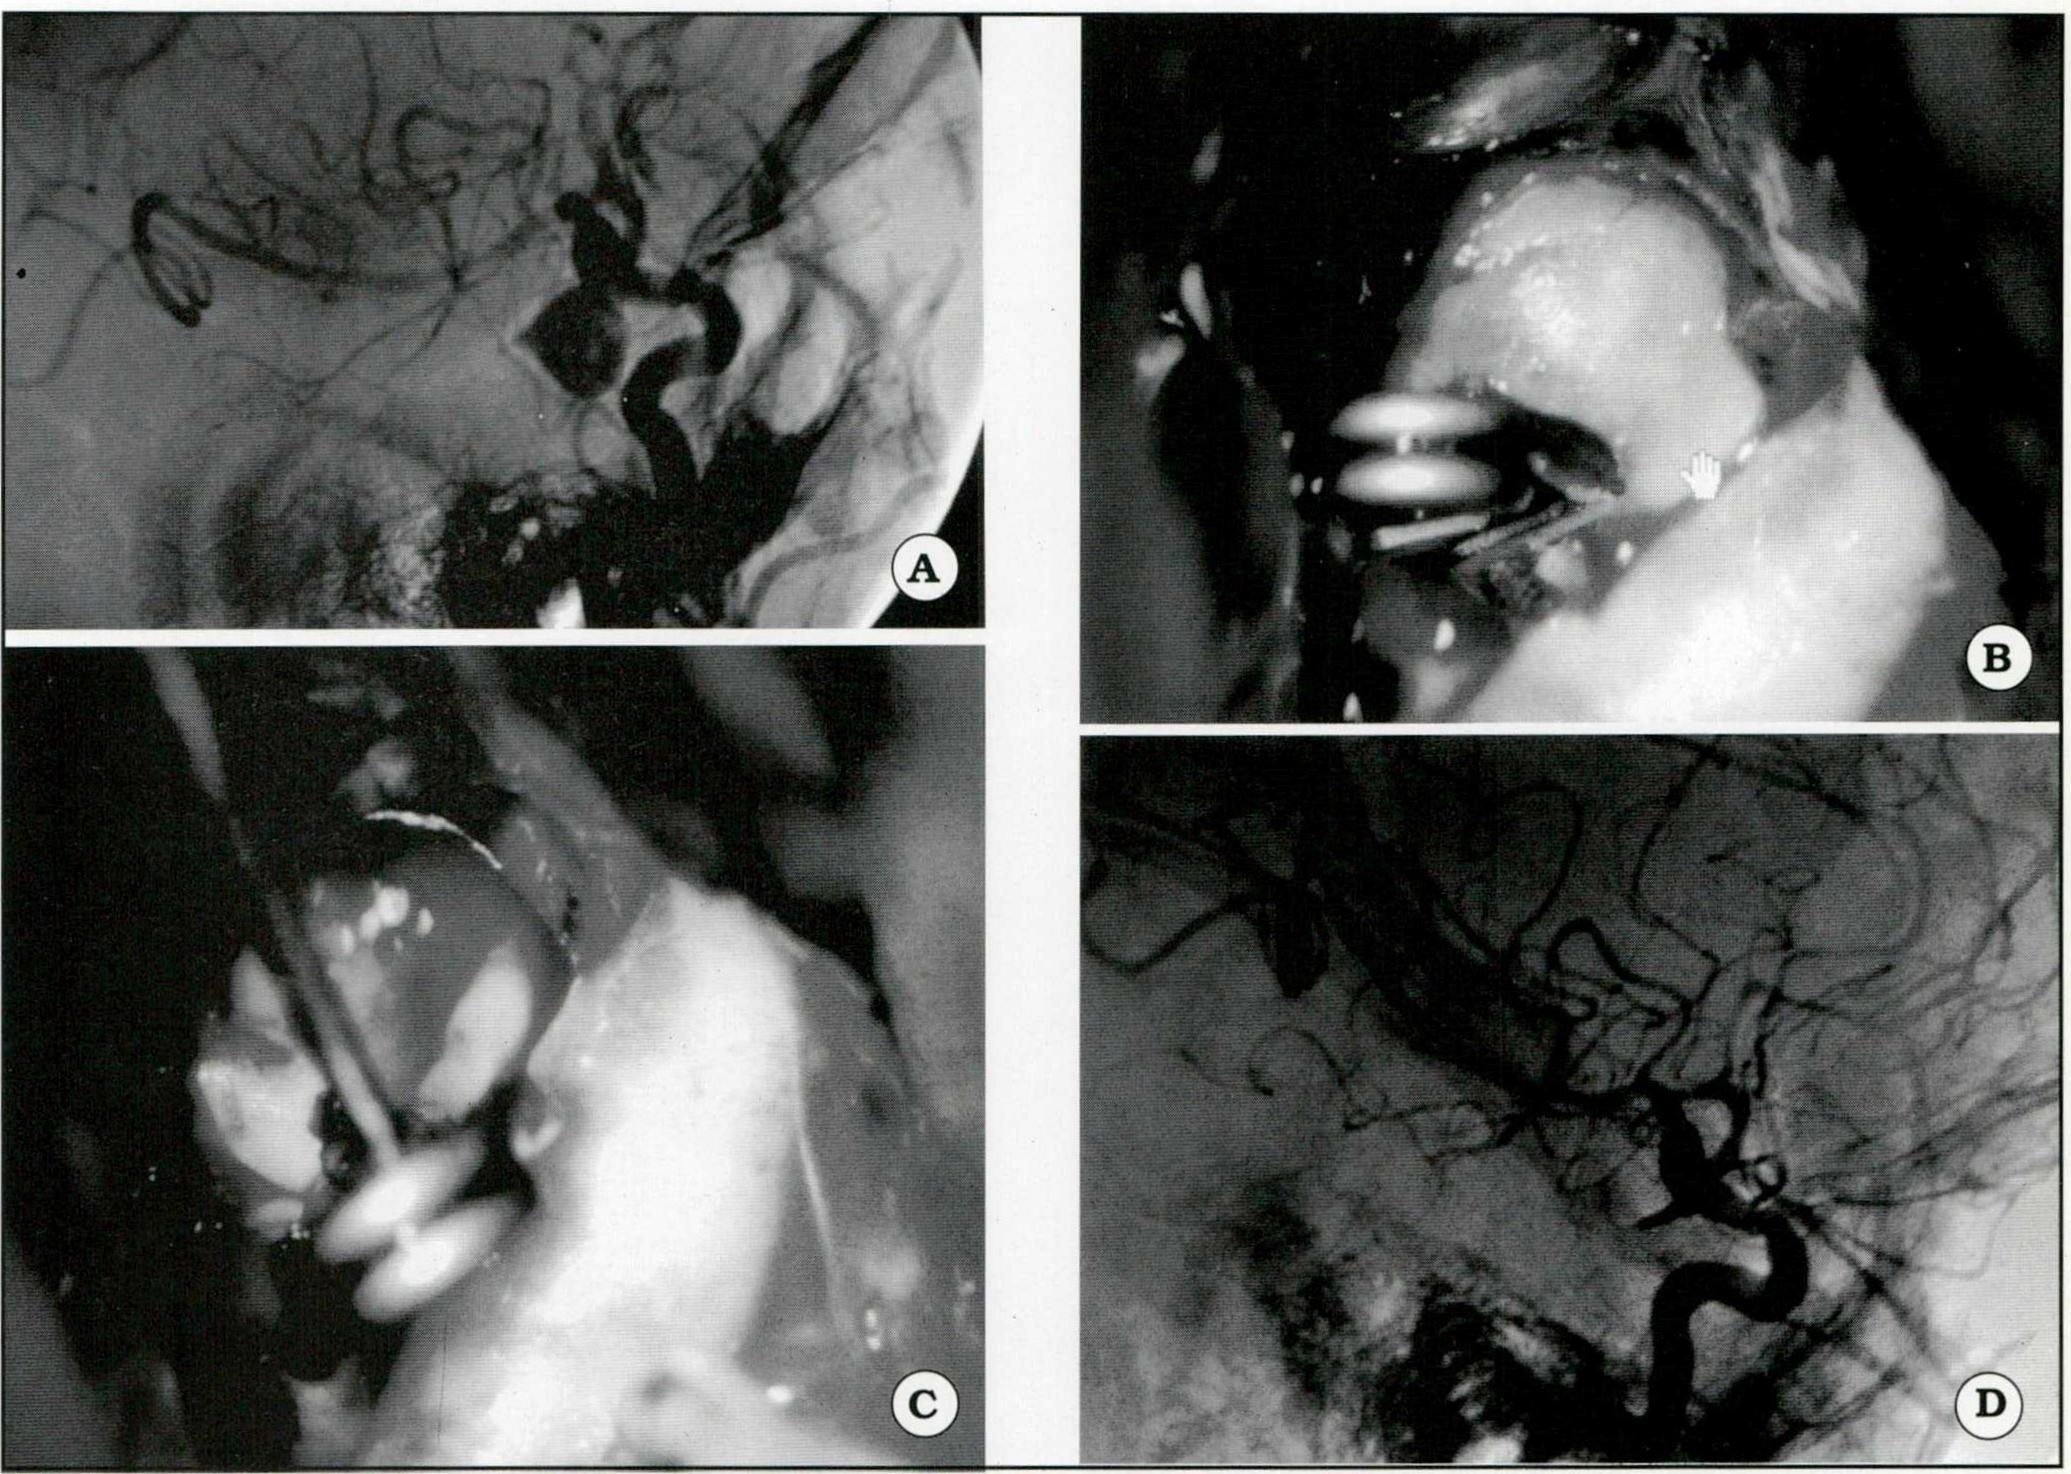

Se ejemplifican iconográficamente las siguientes situaciones:

Fig. 1. A. Angiografía que muestra un aneurisma gigante del segmento comunicante posterior. B. Imagen intraoperatoria. Se observa el clipado del cuello aneurismá tico. C. Clipado del aneurisma. Se realizó punción del saco, maniobra cuyas ventajas se describen en el texto. D. Control angiográfico postoperatorio.